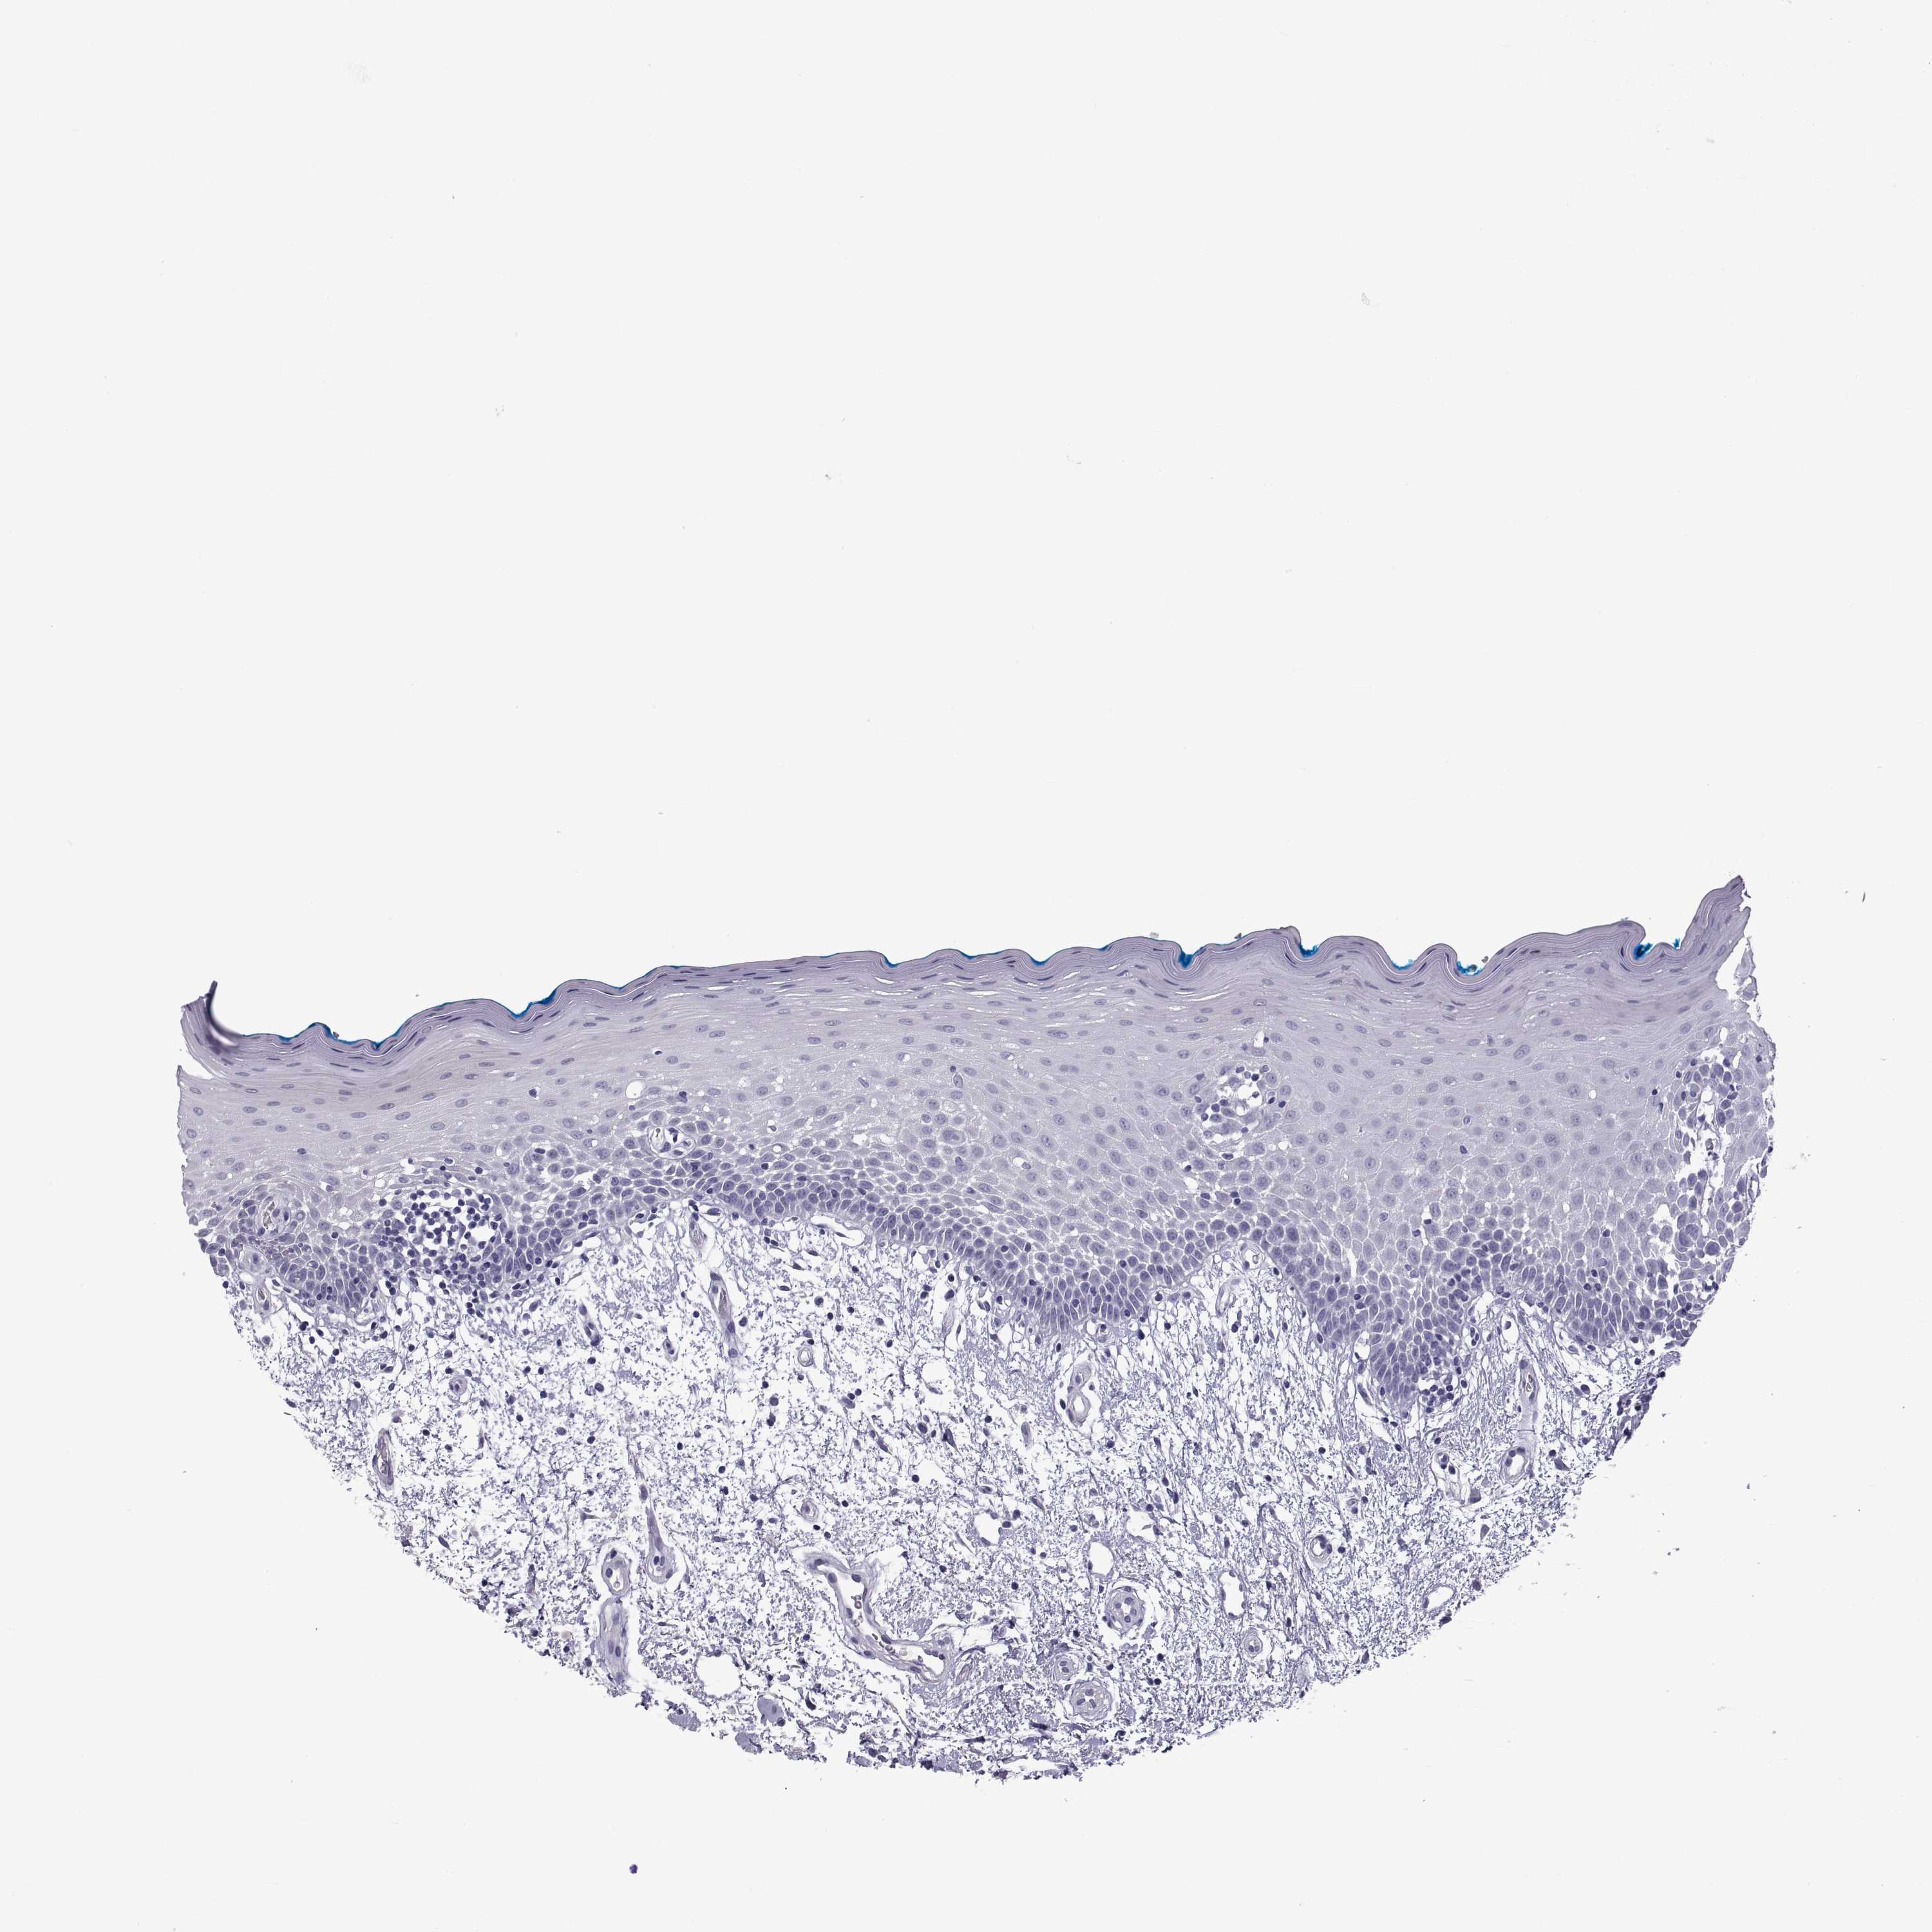

TISSUE PRIMARY DATA ORAL MUCOSA Show tissue menu

Oral mucosa

ORAL MUCOSA - Antibody stainingi

Antibody staining in the annotated cell types in the current human tissue is reported as not detected, low, medium, or high, based on conventional immunohistochemistry profiling in selected tissues. This score is based on the combination of the staining intensity and fraction of stained cells.

Each image is clickable and will lead to virtual microscopy that enables deeper exploration of all samples and also displays staining intensity scores, fraction scores and subcellular localization as well as patient and tissue information for each sample.

Antibody HPA001193Antibody HPA002820

Squamous epithelial cells MediumNot detected